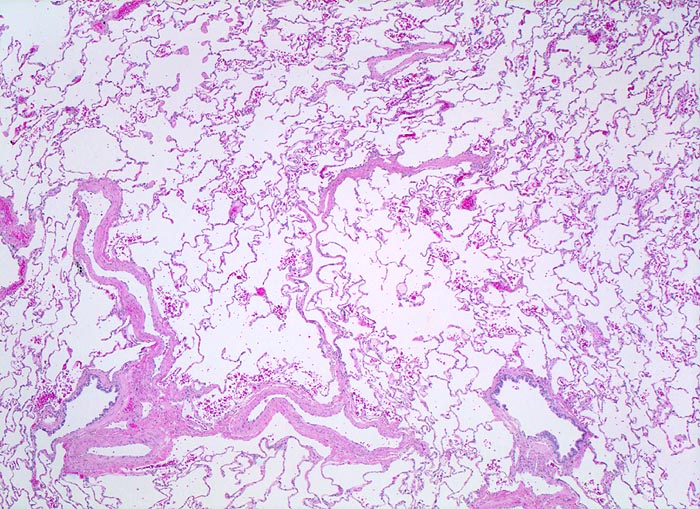

PathoPic ID 4367 - normales Lungenparenchym

normales Lungenparenchym

Normalbefund

Lunge

Lunge, Mediastinum mit Thymus

Die

Lungenarterienäste verlaufen zusammen mit den

respiratorischen Bronchiolen. Die

Lungenvenenäste verlaufen dagegen unabhängig von den Luftwegen im Parenchym. Die Alveolarsepten sind zart. In den Alveolen findet sich entnahmebedingt etwas Blut.

Histologie

25

24

männlich